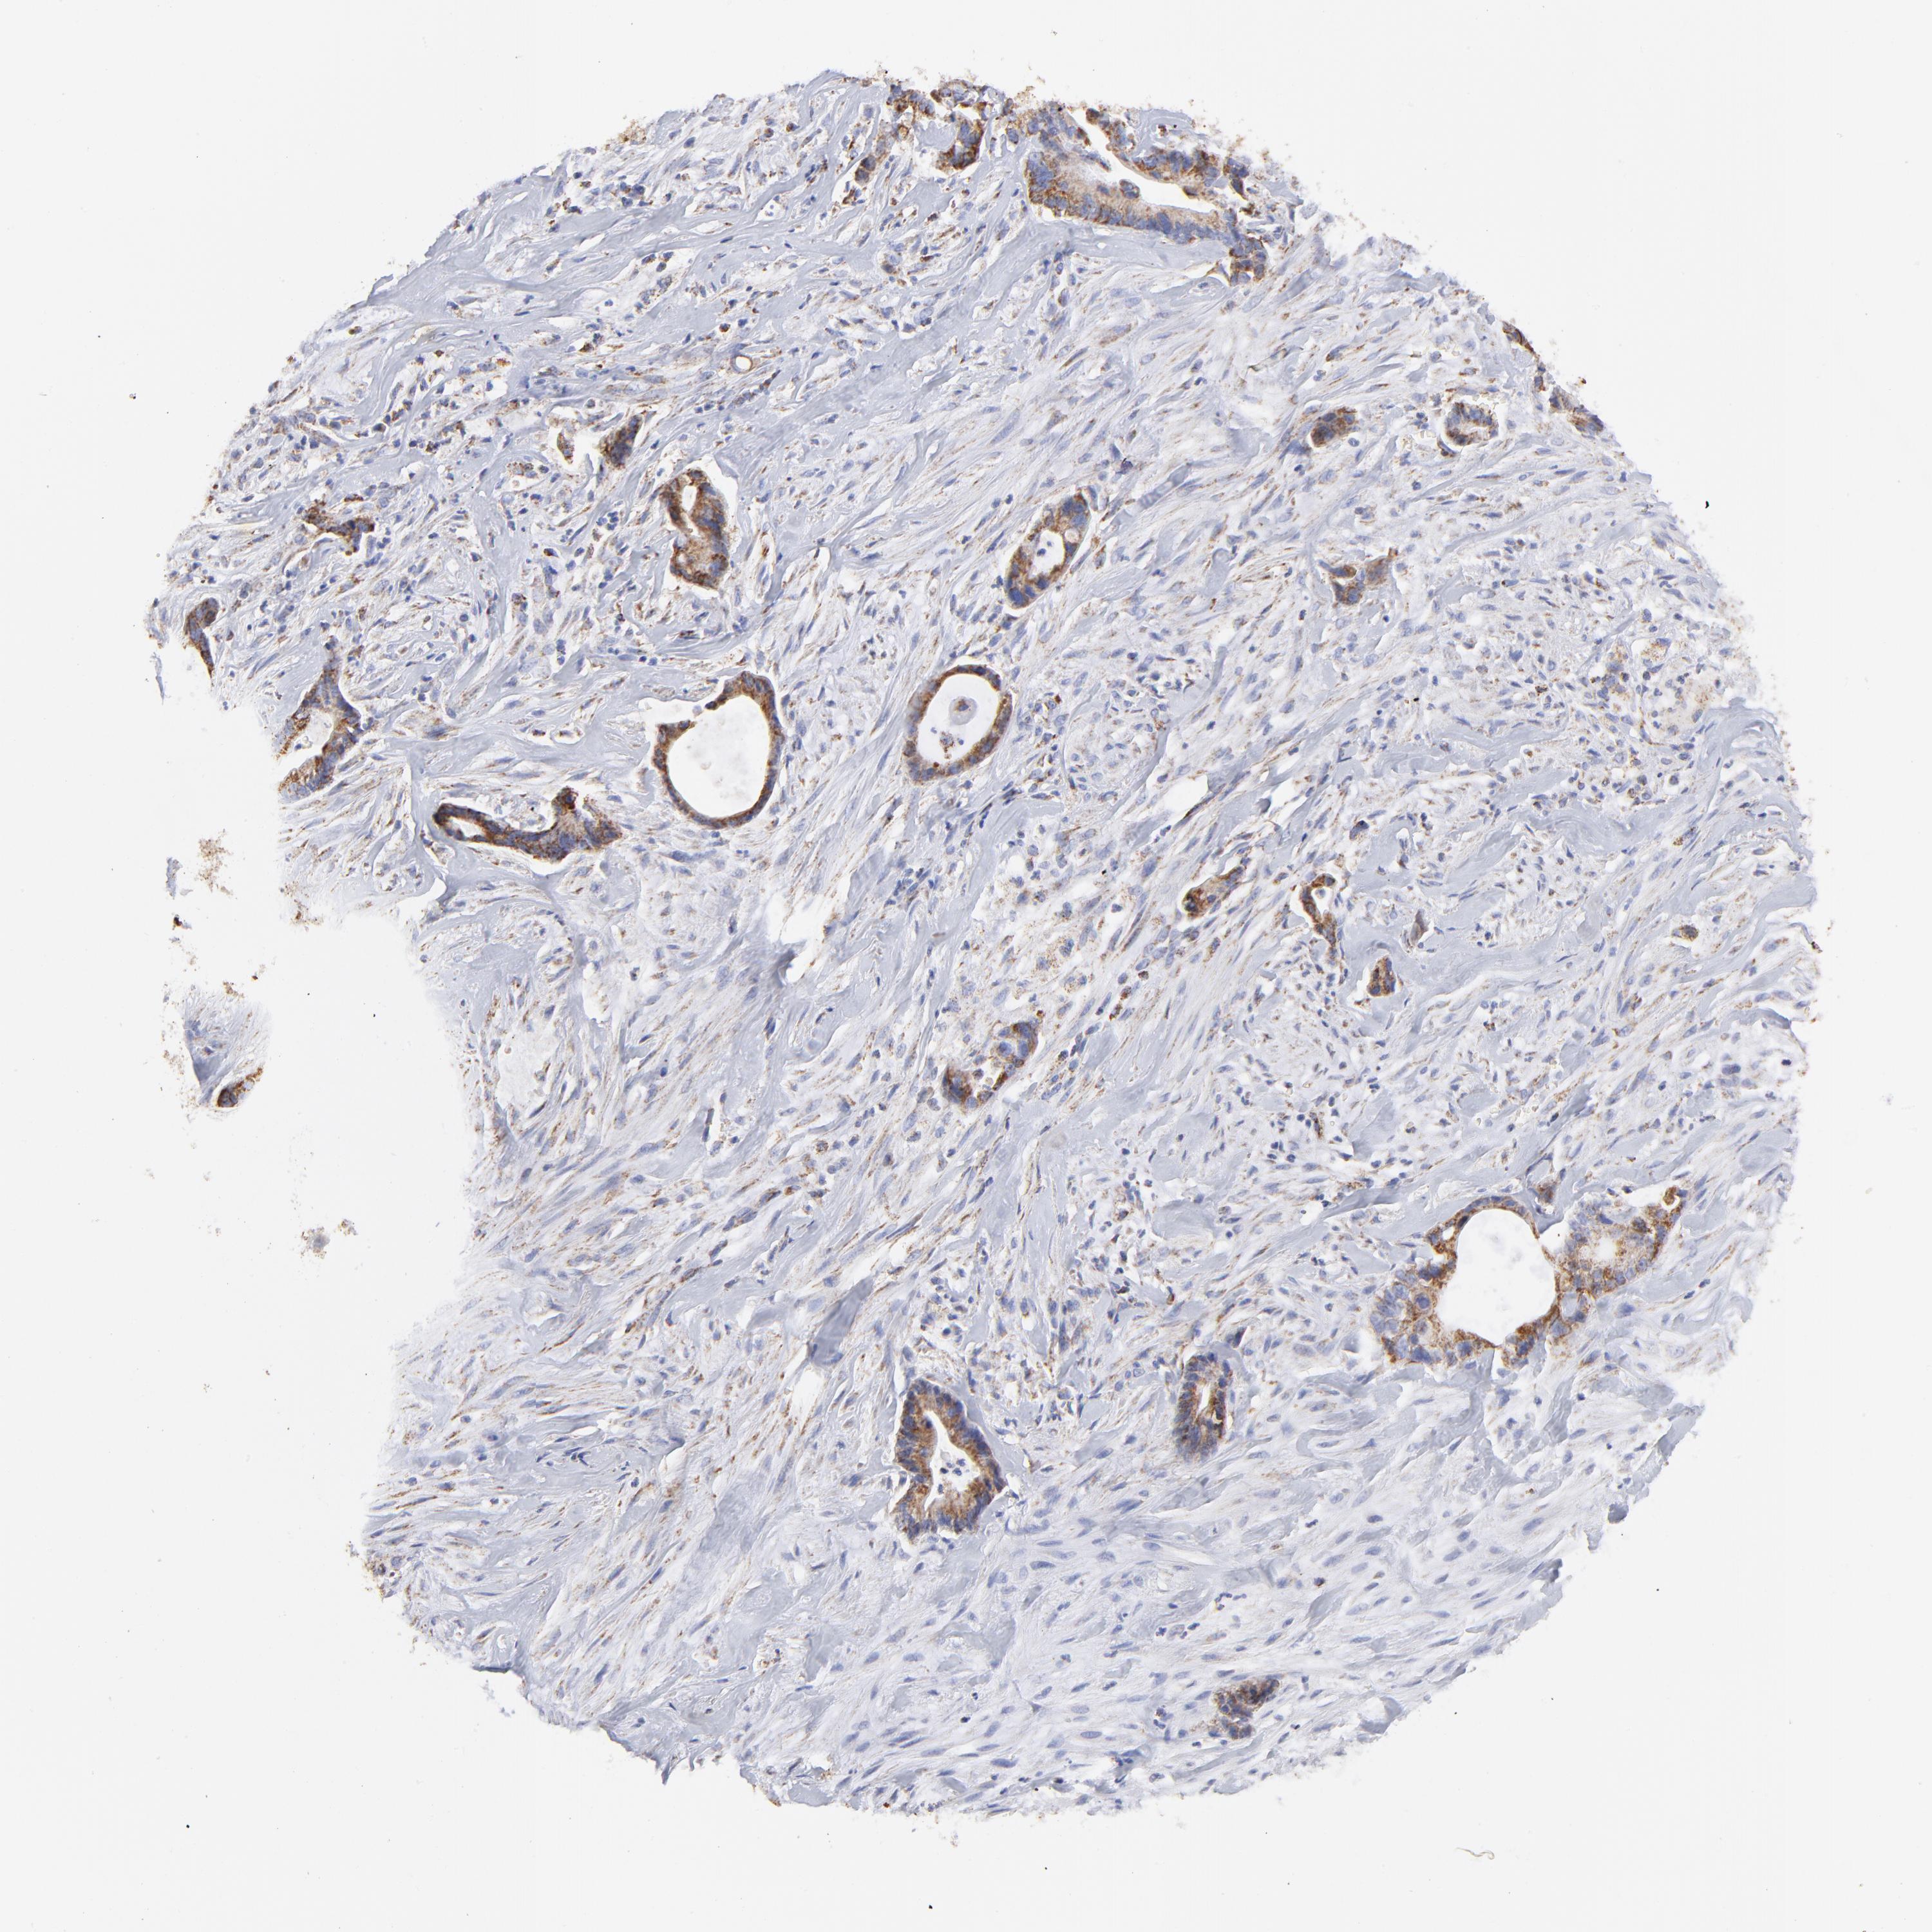

LIVER CANCER - Protein expressioni

A mouse-over function shows sample information and annotation data. Click on an image to view it in a full screen mode. Samples can be filtered based on level of antibody staining by selecting one or several of the following categories: high, medium, low and not detected. The assay and annotation is described here.

Note that samples used for immunohistochemistry by the Human Protein Atlas do not correspond to samples in the TCGA dataset.

Antibody stainingi

Antibody staining in the annotated cell types in the current human tissue is reported as not detected, low, medium, or high, based on conventional immunohistochemistry profiling in selected tissues. This score is based on the combination of the staining intensity and fraction of stained cells.

Each image is clickable and will lead to virtual microscopy that enables deeper exploration of all samples and also displays staining intensity scores, fraction scores and subcellular localization as well as patient and tissue information for each sample.

Antibody HPA002485

Antibody CAB004080

Staining

High

Medium

Low

Not detected

Intensity

Strong

Moderate

Weak

Negative

Quantity

>75%

75%-25%

<25%

None

Location

Nuclear

Cytoplasmic/membranous

Cytoplasmic/membranous,nuclear

Cholangiocarcinoma

Carcinoma, Hepatocellular, NOS